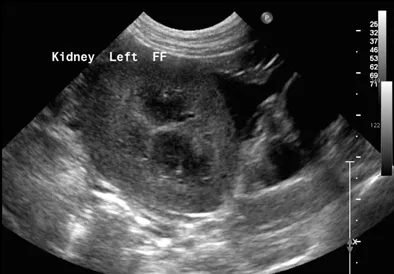

CASE 2 Case 2 is the same dog as case 1. On abdominal ultrasound, the kidneys were slightly enlarged and a small amount of perirenal fluid was visualized (2). Leptospirosis is suspected as the underlying disease.

2